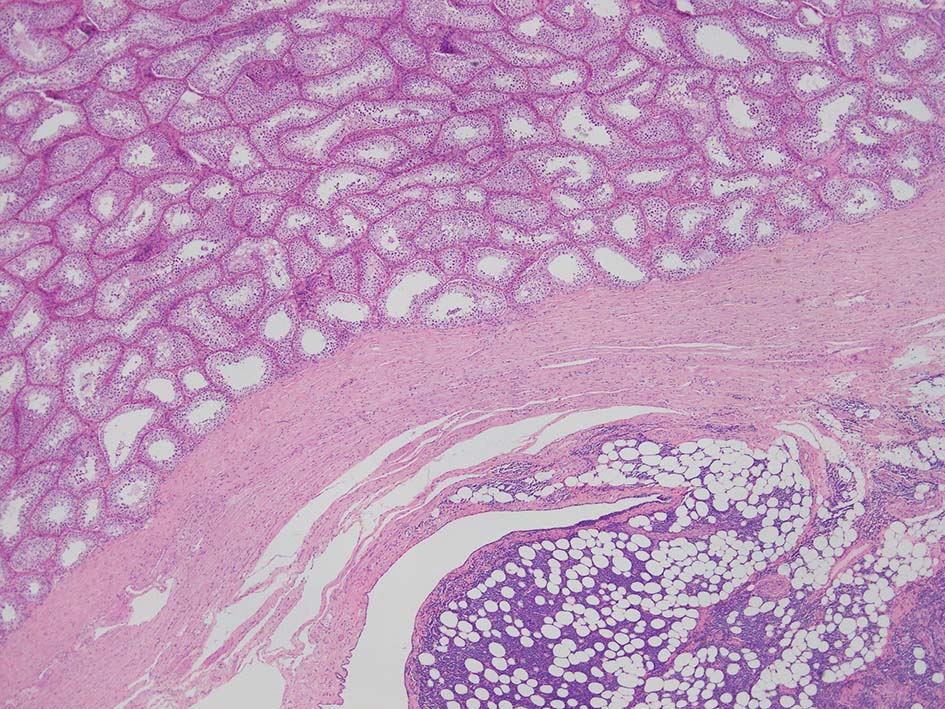

loupe像Aの領域: 精細管をスペアするように, 小型リンパ球優位, 一部中型のlymphoid cellsがシート状密に浸潤増殖する. tubulesのほとんどにはlymphoid cellsが浸潤していないが, LELに似たようなlympho-tubular lesionが少数認められた. x400高倍率では, 増殖細胞は, 粗く, 凝集したクロマチンをもつ類円形, non-cleavedな核をもつ細胞質の乏しいlymphoid cellsである. 核小体か凝集したクロマチンかわかりにくい.

白膜には密に腫瘍性リンパ球が浸潤増殖し, 肥厚, 一部は上図loupe像のように, 腫瘤を形成している. 浸潤リンパ球は精巣実質内よりも, やや大きく, 多稜形, くびれのある核をもち, クロマチンは淡明で核小体が明瞭になってきている.

精巣上体, 精巣周囲脂肪織への浸潤, 精巣実質, 白膜の非浸潤部